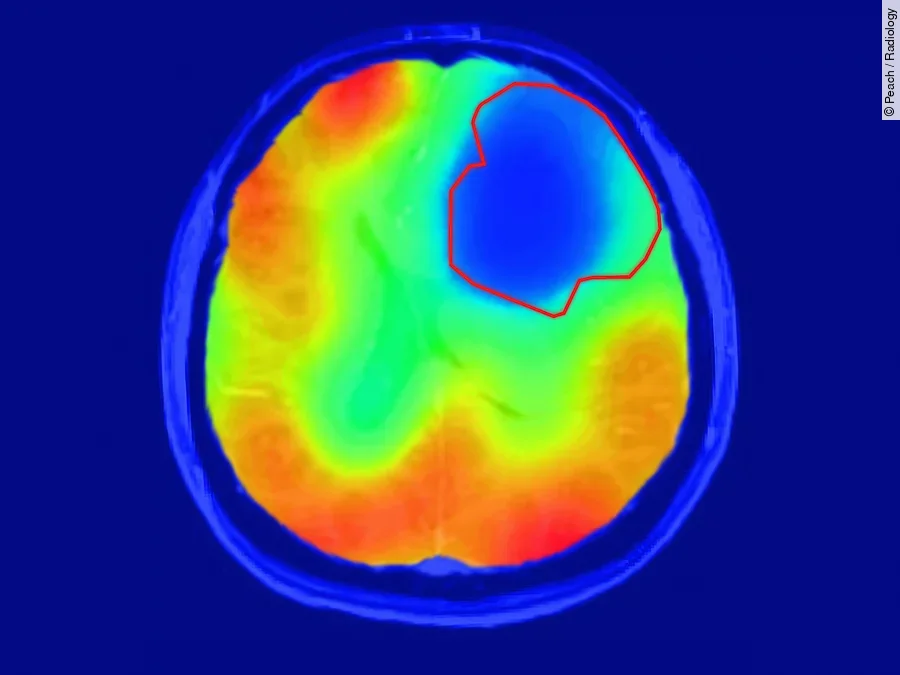

„Wir haben uns die Frage gestellt, ob sich diese Besonderheit im MRT sichtbar machen lässt", sagt der Arzt und Physiker Daniel Paech vom Deutschen Krebsforschungszentrum (DKFZ) in Heidelberg. Herkömmliche MRT-Untersuchungen können lediglich strukturelle Veränderungen sichtbar machen. Die neue Technik der DKFZ-Forscher kommt ganz ohne Radioaktivität aus und zeigt zudem sehr spezifisch den Sauerstoff-abhängigen Stoffwechsel des Gewebes. Die Wissenschaftler verwenden eine stabile, nicht radioaktive Variante des Sauerstoffs, 17O2, die in geringen Mengen auch in der Atemluft vorkommt. Die Probanden atmen diesen besonderen Sauerstoff in angereicherter Form ein. Überall, wo in den Körpergeweben Sauerstoff verstoffwechselt wird, geht 17O2 eine Verbindung mit Wasserstoff ein. Dadurch wird es im Magnetfeld des MRT nachweisbar. Gewebe, das viel Sauerstoff umsetzt, erscheint daher im Bild hell.

Die DKFZ-Wissenschaftler um Paech und seinen Kollegen Sebastian Niesporek haben das Prinzip zunächst bei drei gesunden Probanden durchgespielt. Wie erwartet lassen deren Gehirne in der Bildgebung einen hohen Sauerstoffumsatz erkennen. Dann untersuchten die Forscher zehn Probanden, bei denen ein Gehirntumor diagnostiziert worden war, mit der neuen Sauerstoff-MRT. „Das Ergebnis war wirklich eindrücklich: Die Tumoren erschienen im Bild als dunkle Flecken, weil hier kein Stoffwechsel mit Sauerstoff stattfand“, schildert Paech. „Uns hat überrascht, dass dies sowohl bei höhergradigen aggressiven Tumoren als auch bei weniger aggressiven niedriggradigen Tumoren der Fall war.“ Bislang war nicht klar, ob der Warburg-Effekt auch bei niedriggradigen Hirntumoren gleichermaßen eine Rolle spielt.

Damit haben die DKFZ-Forscher nicht nur neue Erkenntnisse über die Biologie von Gehirntumoren gewonnen. Sie haben auch eine Technik in der Hand, die das Zeug für eine verbesserte Charakterisierung von Tumorgeweben hat. „Wir sehen das Verfahren als ergänzend zur strukturellen MRT-Bildgebung, um Unterschiede zwischen Tumor und gesundem Gewebe auszumachen", so Paech. „Die zusätzlichen Informationen könnten künftig dabei helfen, Tumoren anhand ihres besonderen Stoffwechsels noch präziser zu charakterisieren.“